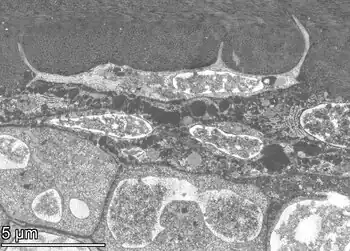

![]() Transverse section of a bone | |

An osteocyte, an oblate-shaped type of bone cell with dendritic processes, is the most commonly found cell in mature bone. It can live as long as the organism itself.[1] The adult human body has about 42 billion of them.[2] Osteocytes do not divide and have an average half life of 25 years. They are derived from osteoprogenitor cells, some of which differentiate into active osteoblasts (which may further differentiate to osteocytes).[1] Osteoblasts/osteocytes develop in mesenchyme.

In mature bones, osteocytes and their processes reside inside spaces called lacunae (Latin for a pit) and canaliculi, respectively.[1] Osteocytes are simply osteoblasts trapped in the matrix that they secrete. They are networked to each other via long cytoplasmic extensions that occupy tiny canals called canaliculi, which are used for exchange of nutrients and waste through gap junctions.

Structure

Osteocytes have a stellate shape, approximately 7 micrometers deep and wide by 15 micrometers in length.[3] The cell body varies in size from 5–20 micrometers in diameter and contain 40–60 cell processes per cell,[4] with a cell to cell distance between 20–30 micrometers.[3] A mature osteocyte contains a single nucleus that is located toward the vascular side and has one or two nucleoli and a membrane.[5] The cell also exhibits a reduced size endoplasmic reticulum, Golgi apparatus and mitochondria, and cell processes that radiate largely towards the bone surfaces in circumferential lamellae, or towards a haversian canal and outer cement line typical of osteons in concentric lamellar bone.[5] Osteocytes form an extensive lacunocanalicular network within the mineralized collagen type I matrix, with cell bodies residing within lacunae, and cell/dendritic processes within channels called canaliculi.[6]